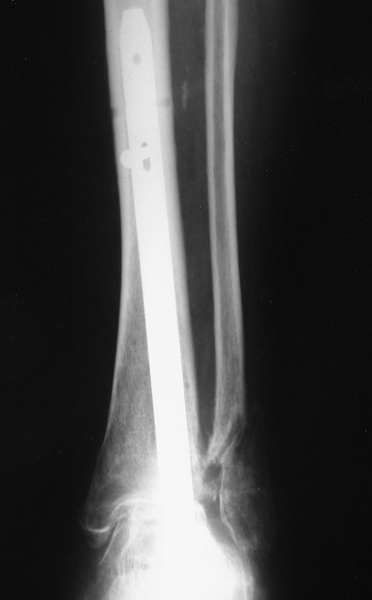

Уважаемые коллеги! Обратилась женщина 45 лет. Травма 2 года назад (март 2005 г.) - открытый 2-х лодыжечный перелом левой голени.

К сожалению, рентгенархив недоступен. Лечилась на вытяжении, затем гипсовой повязкой. Рана у внутренней лодыжки зажила вторичным натяжением. Сращения не наступило. В июне 2005 г. выполнялся артродез по Кэмпбеллу, фиксация в гипсовой повязке 3.5 мес. Сейчас нога полностью неопороспособна, выраженная патологическая подвижность. Признаков инфекции нет. Помогите определиться с методом артродеза, фиксации (КДО?), нужно ли вскрывать сустав, костная пластика? Пациентка, намучавшись за 2 года. "готова на любые эксперименты" (ее слова).Спасибо, с уважением, А. Минервин